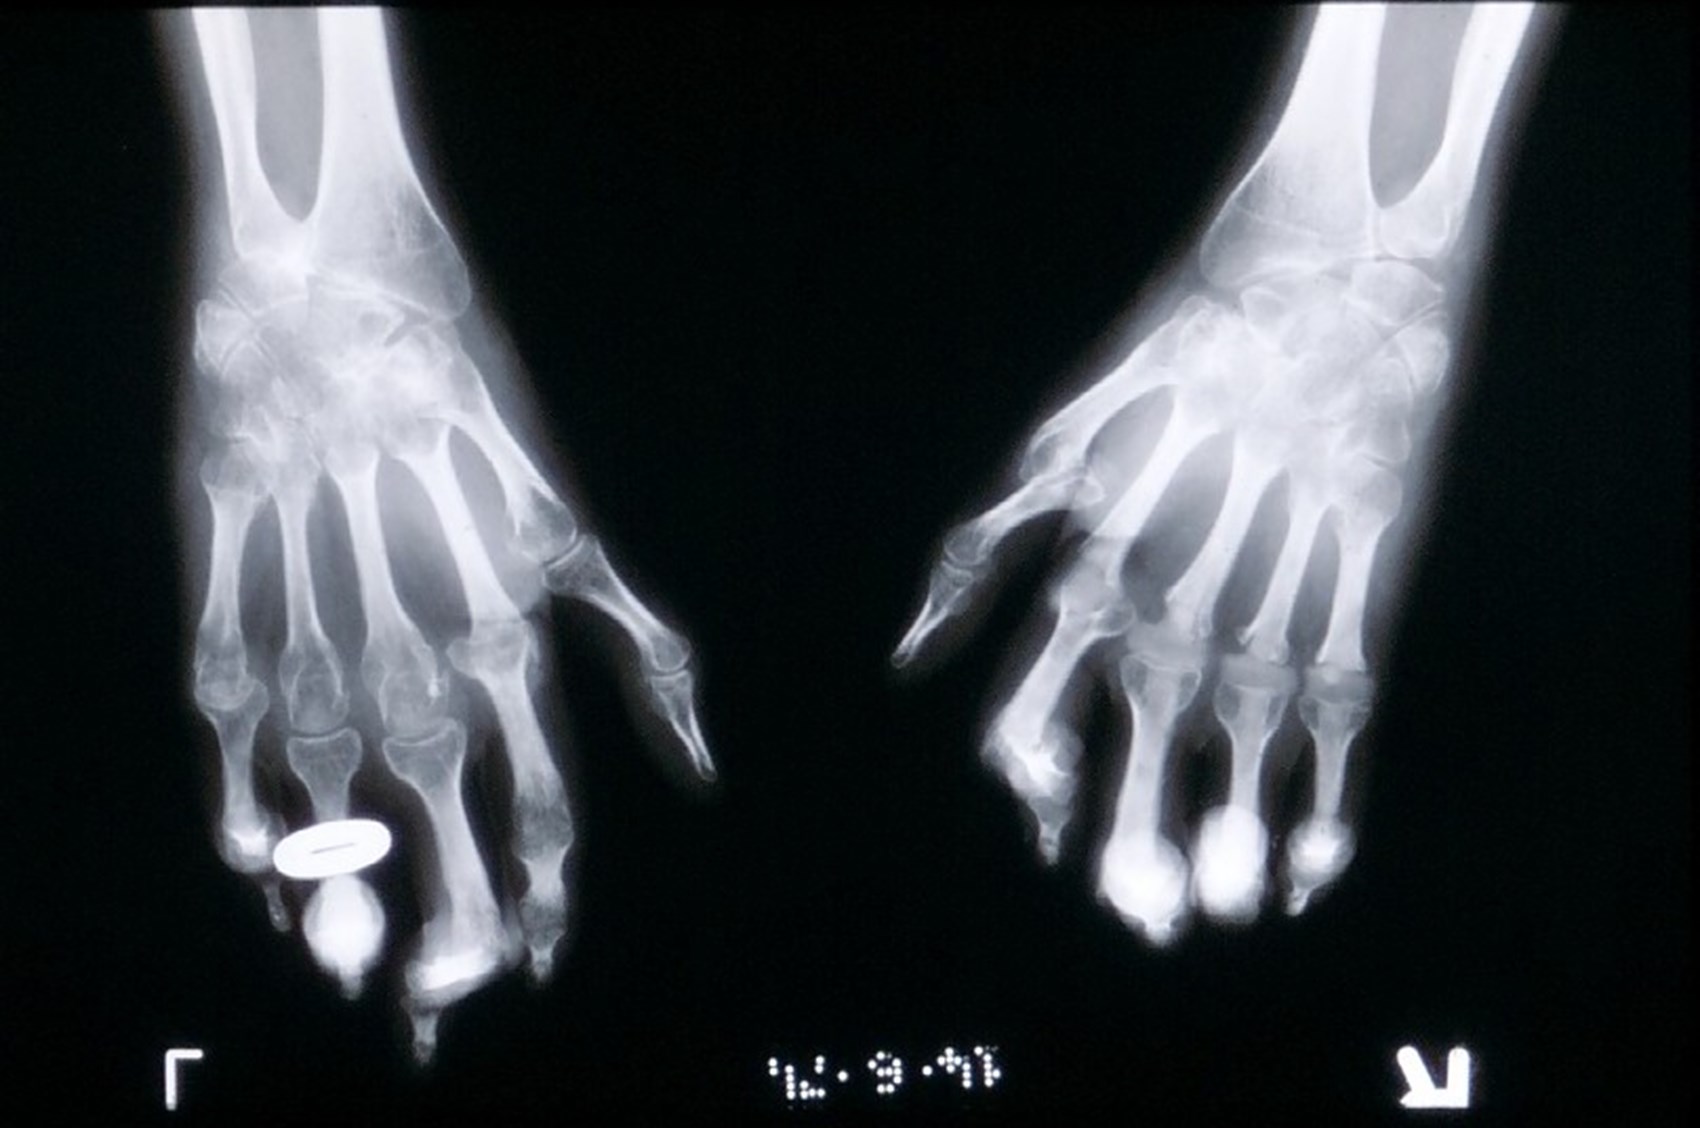

Researchers at the Department of Health Sciences at York have carried out the first randomised controlled trial to study the effects of copper bracelets and magnetic wrist straps on rheumatoid arthritis, 70 patients with active symptoms each wore four different devices over a five-month period, reporting on their pain, disability, and medication use throughout the study. Participants also provided blood samples, after wearing each device for five weeks, in order to monitor changes in inflammation.

According to new findings from the study, copper bracelets and magnet wrist straps have no real effect on pain, swelling, or disease progression in rheumatoid arthritis.